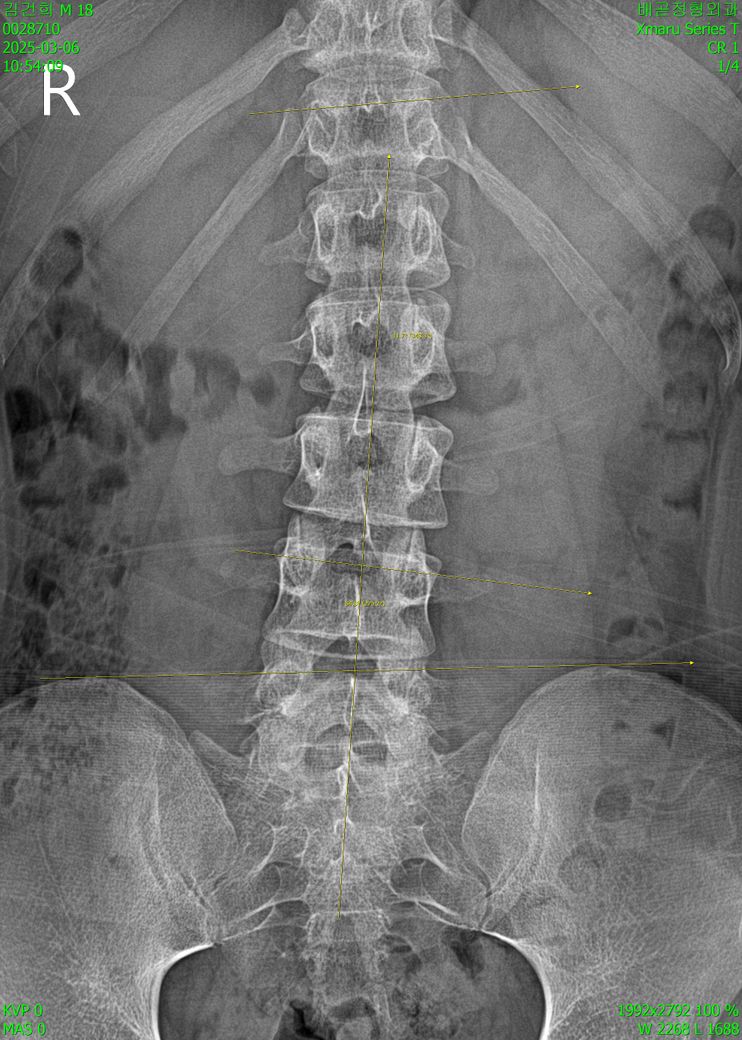

엑스레이 상으로 심하게 휘어져있나요?

문제되는 부분들 전부 지적해주세요 ㅠㅠ

심한 정도도 궁금해요

오늘 진료받고 왔는데 선생님께서

나이에 비해 심하다고 하셔서요 ㅠㅠ

• 1번 째 사진

엑스레이사진을 보니 일단 옆으로 찍은 사진이랑 정면에서 찍은 엑스레이로 확인이 되고 일단 엑스레이상 척추 뼈의 정렬은 크게 틀어지거나 하지는 않은 것으로 보이나 옆으로 보았을때 허리뼈의 만곡이 약간 감소 되어있기는 하지만 통증이 없다면 크게 걱정하실 필요는 없을 것으로 생각되며 평소 자세와 습관등을 고쳐주시고 적절한 운동을 통해 허리의 만곡을 잘 만들어 주시면 좋을 것 같습니다.

좌우 대칭이 맞지않고, 척추의 곡선이 일자에 가까워지는 것으로 보입니다.

사진상으로 많은걸확인할수없지만 약간의 허리측만과 허리커브의감소가보입니다 이럴경우 허리쪽으로 지속적으로 부담이나 스트레스가 생길수있기때문에 허리의 커브를만들어주는동작이나 중립척추를 유지하면서 할수있는 코어운동을 평소에 꾸준하게하는것이 도움이될수있습니다